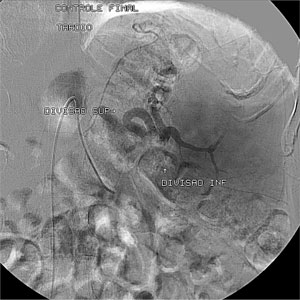

R.F.C, sexo masculino, 68 anos, procedente de Maceió – AL, é portador de hepatite C (genótipo 3a) e de esquistossomose mansônica hepatoesplênica com quadro de hiperesplenismo. Ultrassonografia com doppler de abdome total evidenciou hepatomegalia com sinais de doença parenquimatosa, esplenomegalia e veia esplênica de calibre aumentado. À endoscopia digestiva alta, foi demonstrada gastropatia da hipertensão portal severa, sem erosões antrais, e no hemograma, plaquetopenia (44.600 plaquetas/mm3). O paciente foi submetido à embolização da artéria esplênica (duas sessões) para controle do hiperesplenismo. Com a embolização, 60% do baço foi desvascularizado (Figura 1), havendo aumento do número de plaquetas para 98.200/mm3, e 34 meses após, para 103.000 plaquetas/mm3, possibilitando o tratamento da hepatite.